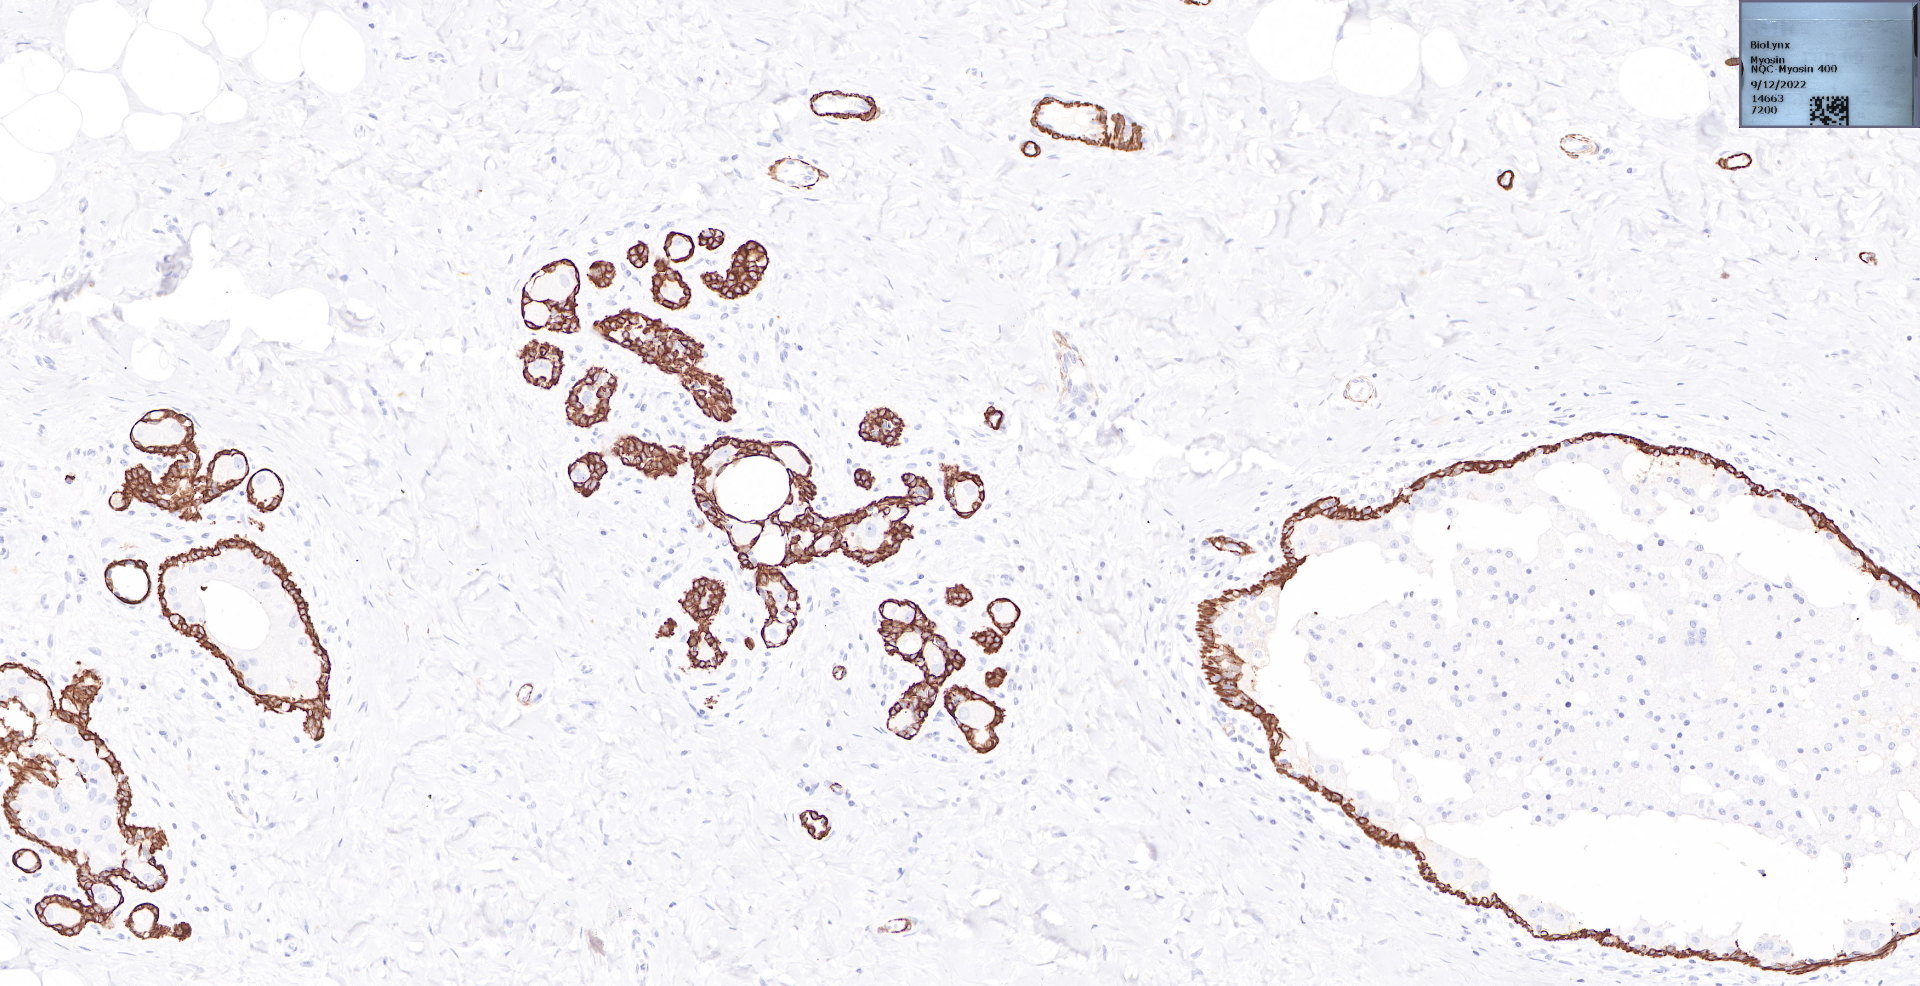

SMH (Smooth Muscle Myosin)

undefined

BP6091 Smooth Muscle Myosin乳腺导管癌染色

BP6091 Smooth Muscle Myosin乳腺增生染色

原位乳腺导管癌.jpg

标题